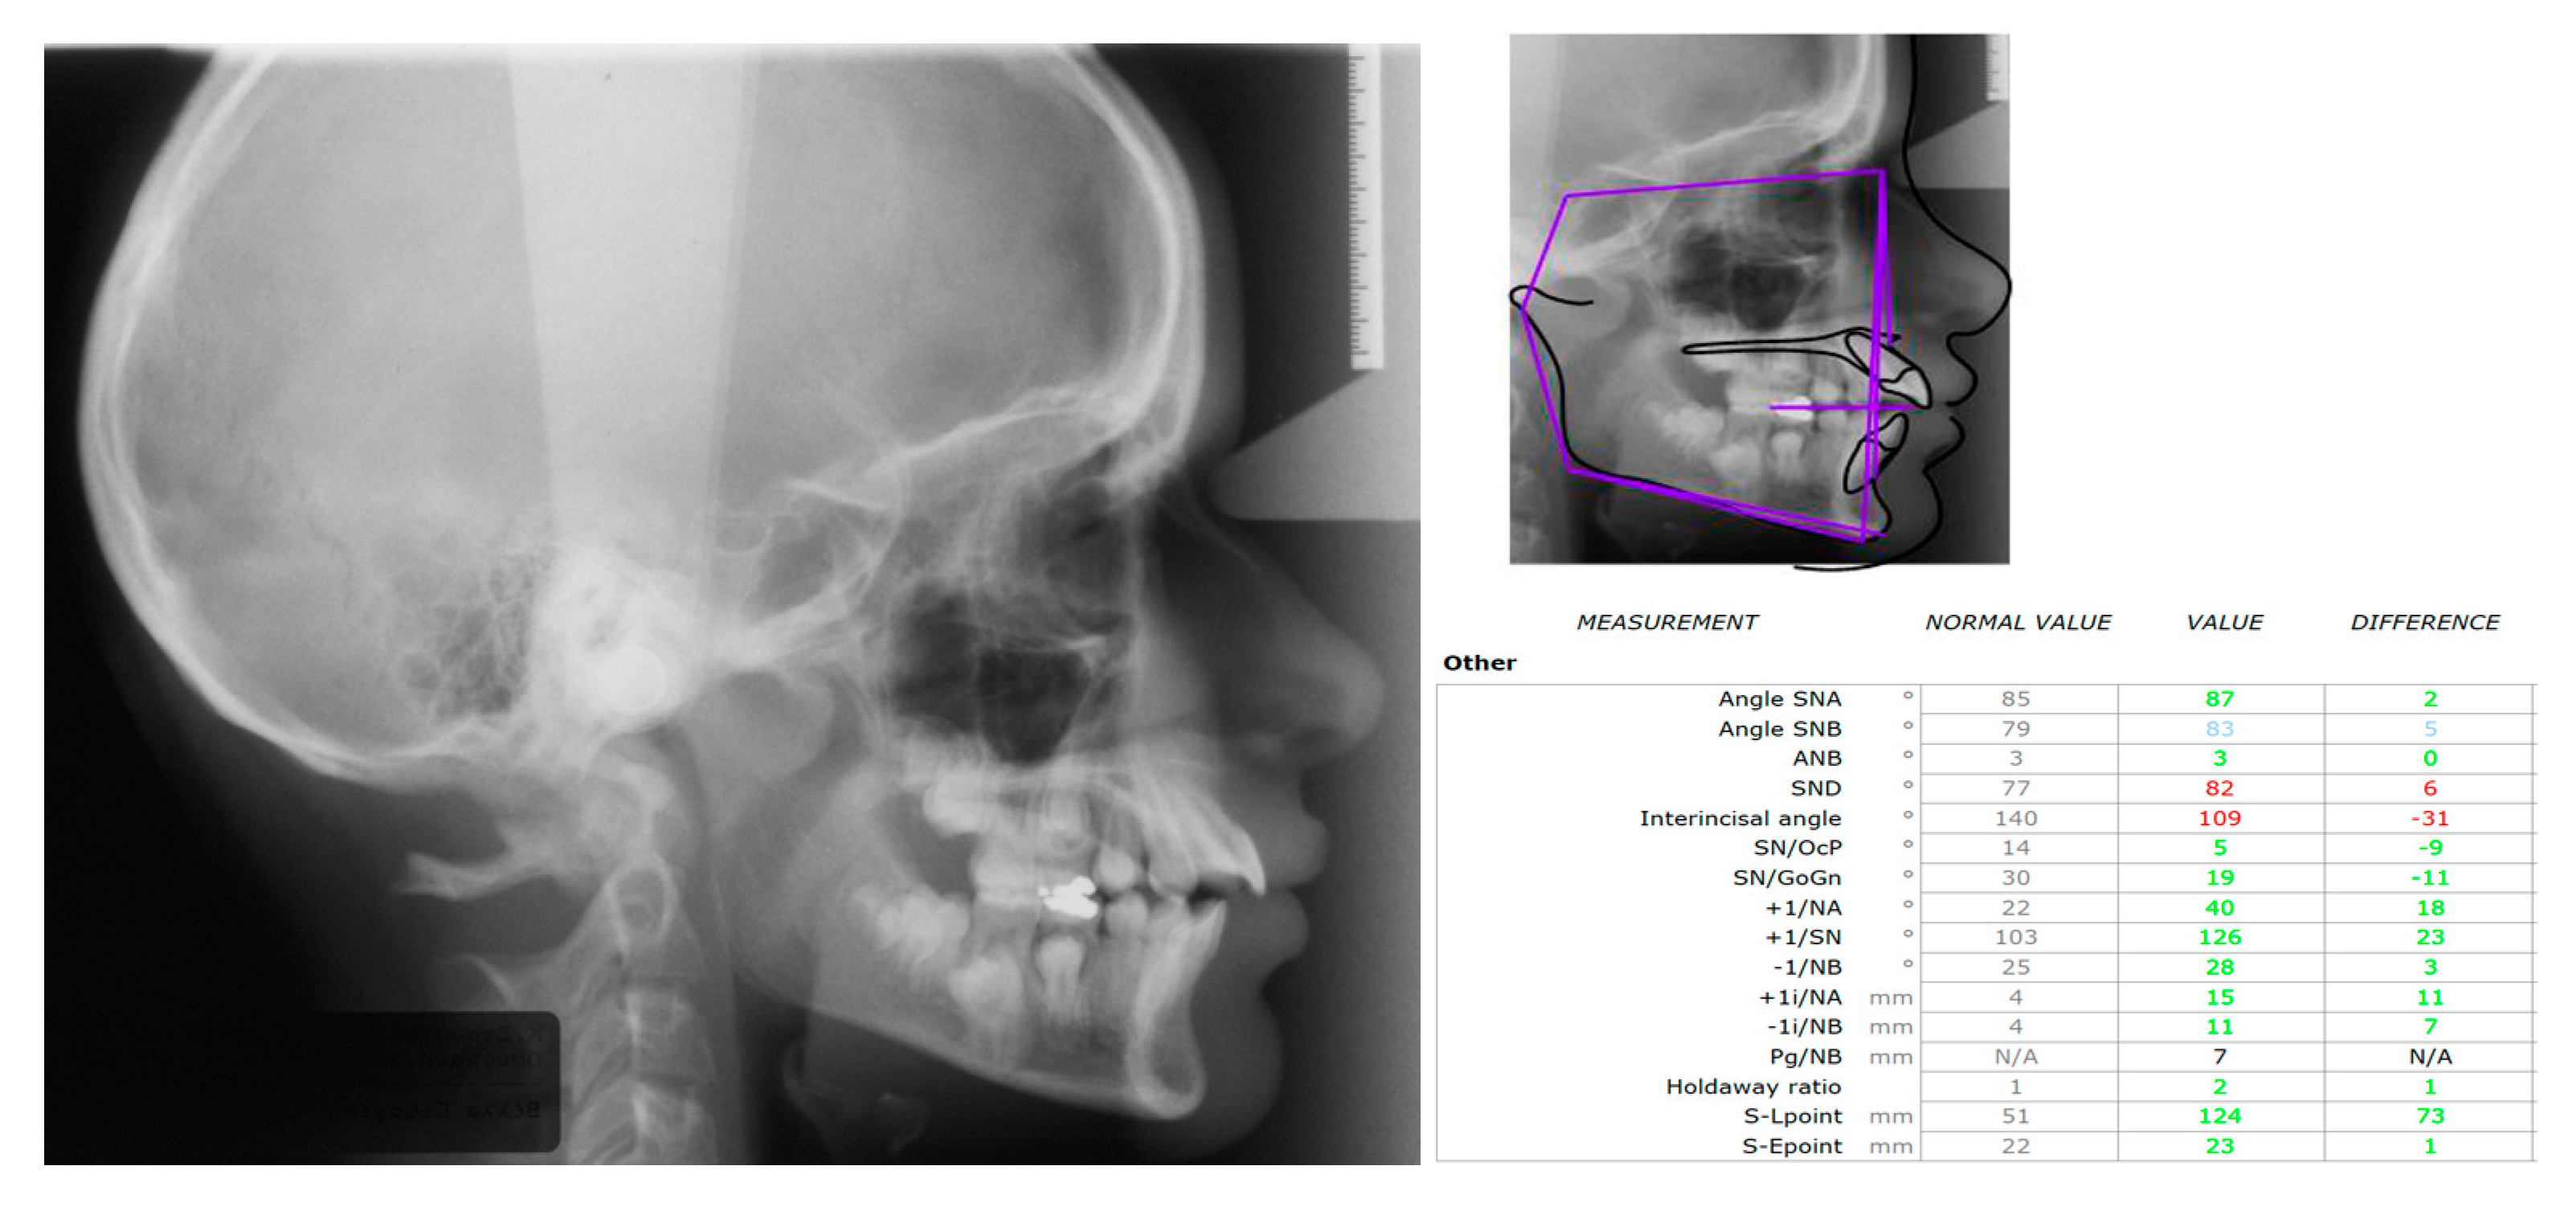

2. Case Presentation